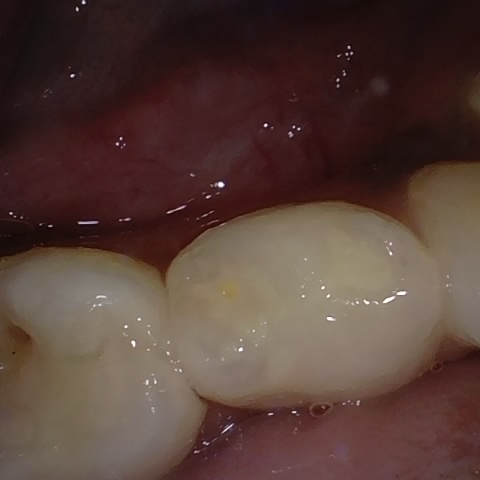

Annotated as "Good"